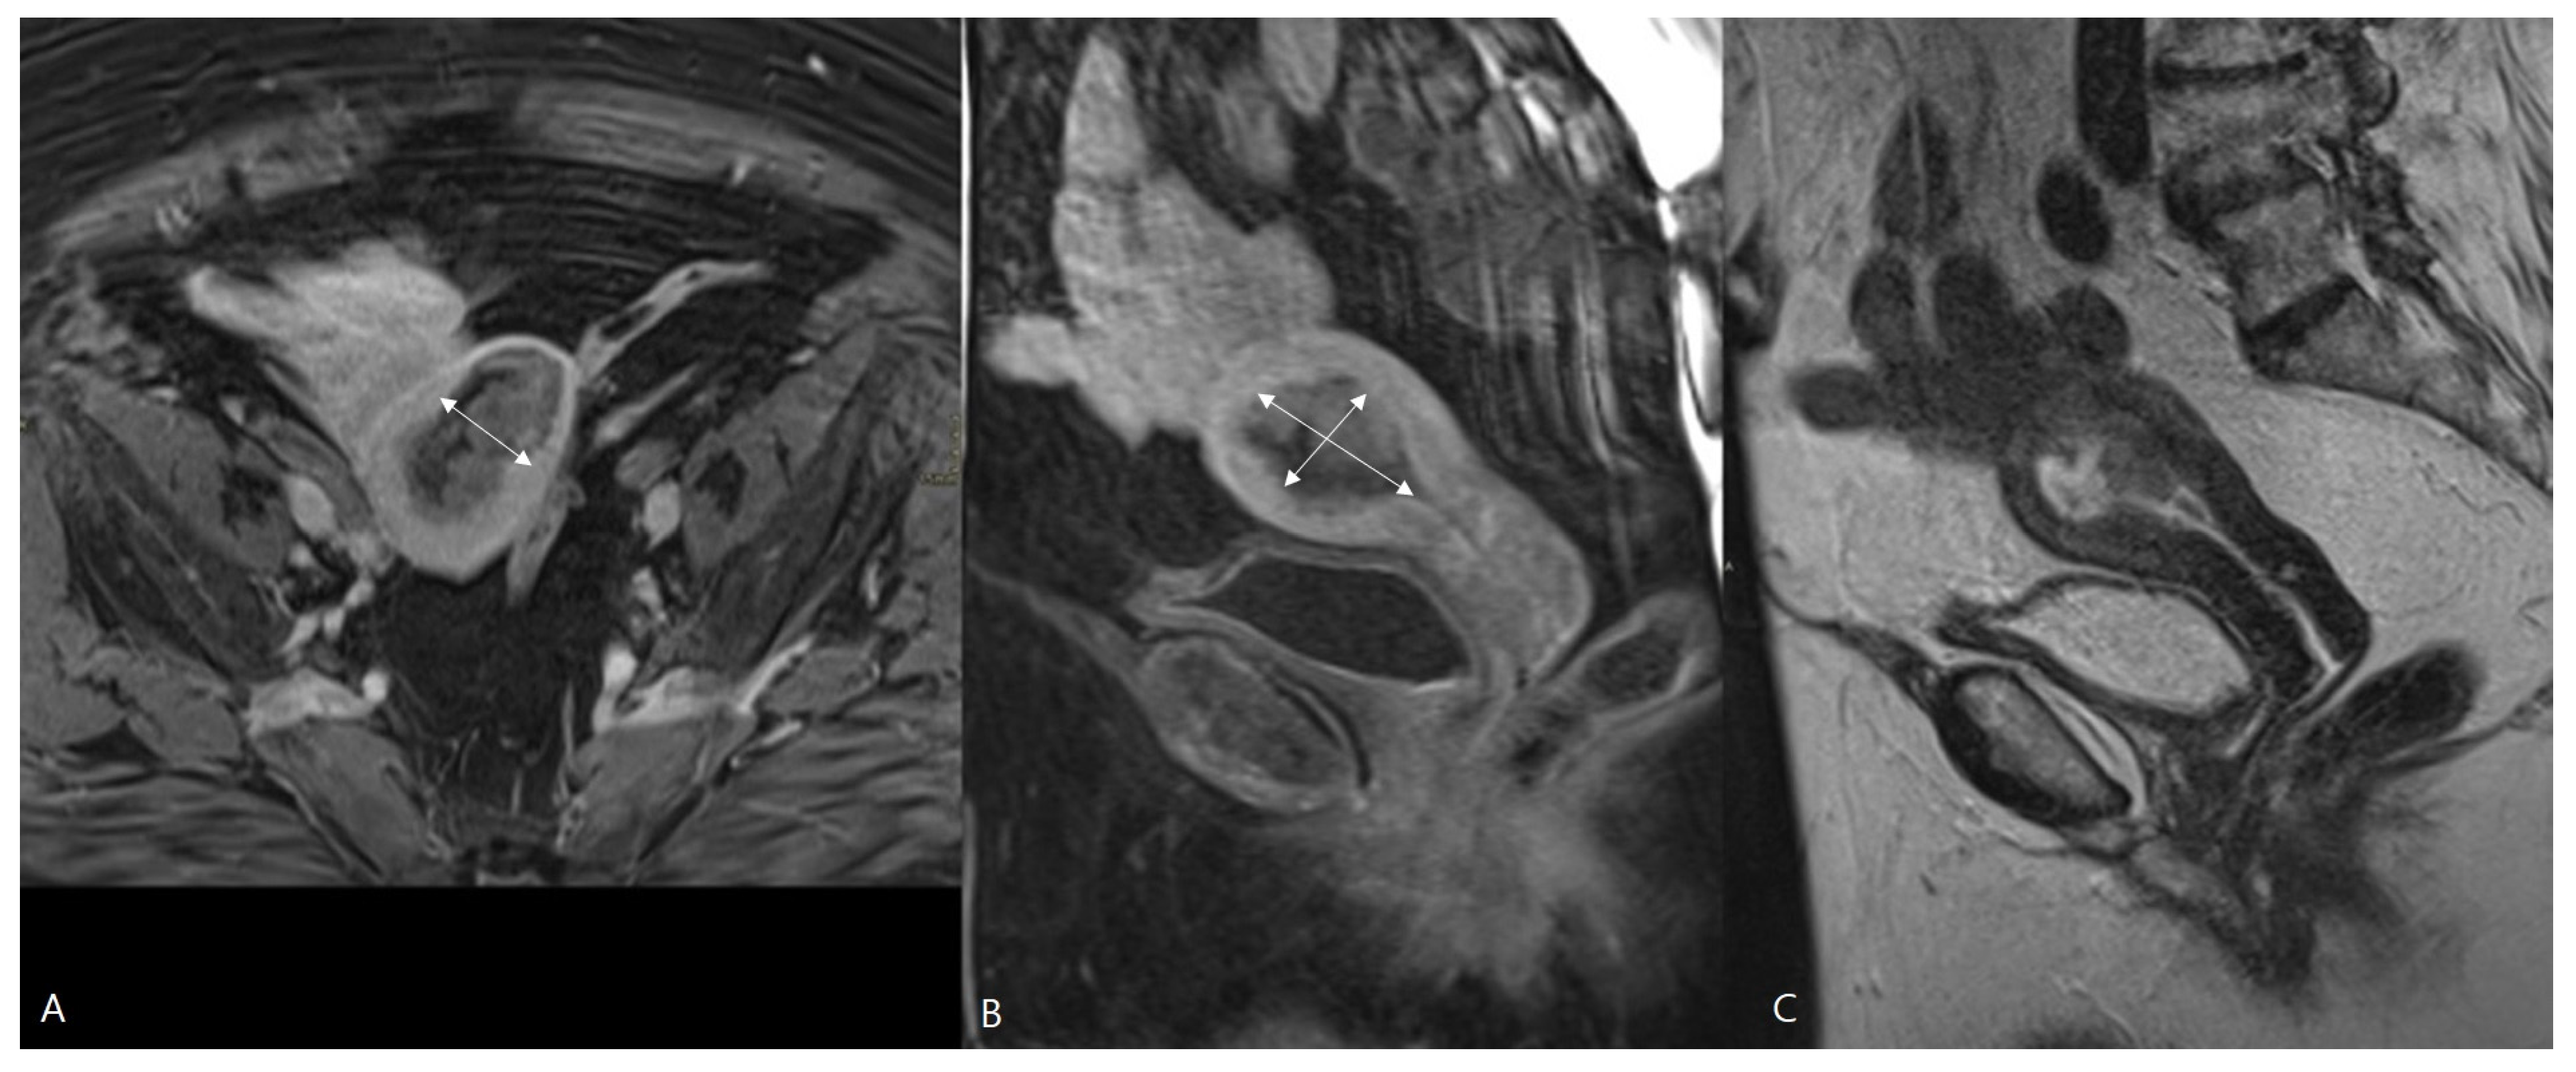

MRI has long been established as a valuable imaging method in the preoperative staging of EC. MRI can assess the depth of myometrial invasion, but histological type and grade can only be determined with endometrial tumor sampling (Figure 2). Preoperative staging with MRI may be advantageous to predict ≥pT1b disease preoperatively to avoid a second surgical procedure for lymphadenectomy [12], but there is ongoing discussion regarding the value of routine MRI in the preoperative assessment of EC [18,26].

Figure 2.

MRI of a pT1b endometrial cancer. T1-weighted images after Gadolinium administration in the axial (A) and sagittal plane (B). Sagittal T2-weighted image (C). The tumor is demonstrated as a heterogenous mass in the uterine cavity, with heterogenous contrast enhancement lower than the surrounding myometrium. The tumor is macroscopically invading the outer half of the myometrium, staged iT1b and confirmed histopathologically pT1b at hysterectomy. The size of the tumor was measured in three directions (white arrows) via MRI. The largest tumor diameter was assessed, and the tumor volume was calculated by the ellipsoid formula (AP × CC × LL × 0.52).